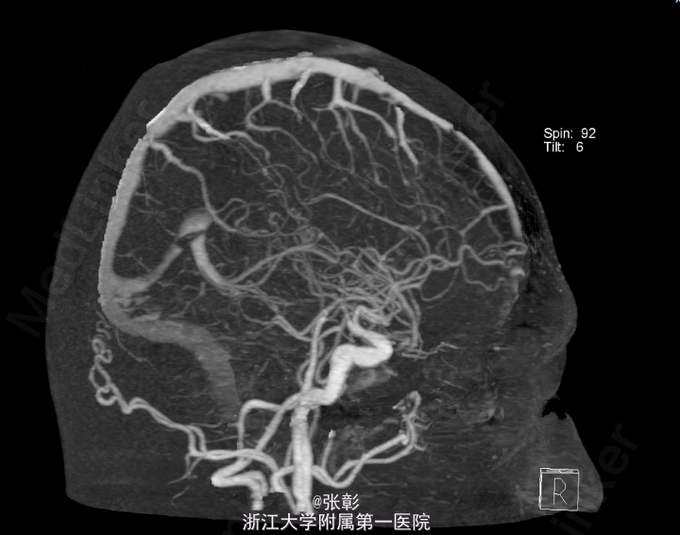

初步诊断:亚急性硬膜下血肿. 入院后行各项检查,(2015-06-24 11:40)血常规(五分类)(全血):白细胞计数9.2×10^9/L、血红蛋白139g/L、血小板计数245×10^9/L、(2015-06-24 10:57)电解质全套(血清):白蛋白45.9g/L、钾3.87mmol/L、钠138.0mmol/L、肌酐79μmol/L、甘油三酯1.89mmol/L↑、C-反应蛋白7.1mg/L、(2015-06-24 14:25)肿瘤标记物全套(男)(血清):癌胚抗原1.2ng/mL、甲胎蛋白1.9ng/mL、癌抗原1996.0U/mL。(2015-06-23 19:42)行CT(头部)检查提示:脑动脉CTA检查未见异常CT征象。右侧额颞顶部硬膜下血肿。进一步行脑血管造影:脑血管造影未见明显异常。给予对症支持治疗。